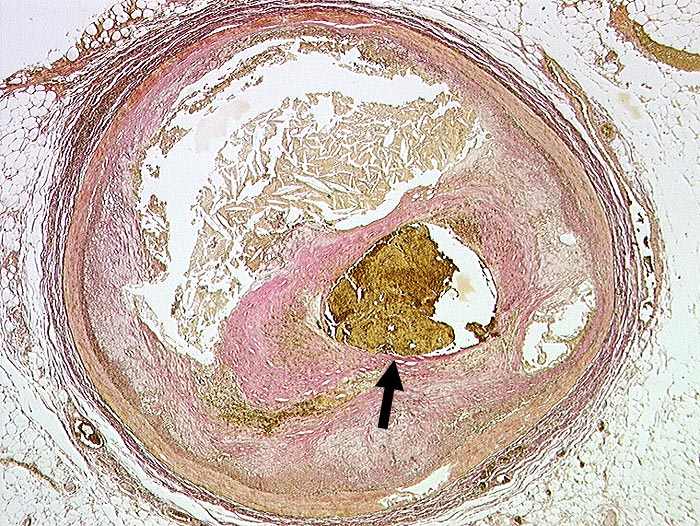

PathoPic ID 98 - Koronarthrombose

Koronarthrombose

vaskulär / Durchblutungsstörung

Arteria coronaris

Kardiovaskuläres System

Exzentrische Stenose von mehr als 75% des Lumendurchmessers. Atherom mit herausgelösten Cholesterinkristallen.

►

Intraluminale frische Thrombose.

Transmuraler akuter Myokardinfarkt mit Myokardruptur bei thrombotischem Verschluss des RIVA.

Diabetes mellitus Typ II und Adipositas.